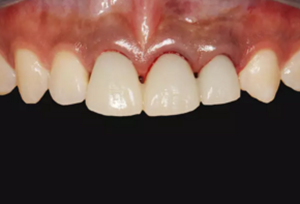

圖2 術(shù)前口內(nèi)像

圖14 術(shù)后4個月口內(nèi)像

圖23 最終修復(fù)后即刻口內(nèi)像

圖25 最終修復(fù)后復(fù)查口內(nèi)像